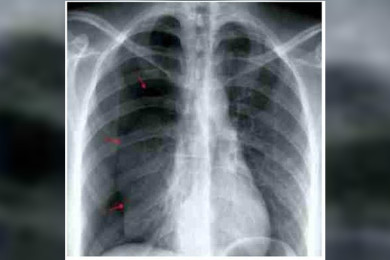

อึ้ง! หญิงวัย34ปีปอดทะลุช่วงเป็นเมนส์ เหตุเยื่อบุมดลูกกระจายเต็มกะบังลม-ปอด